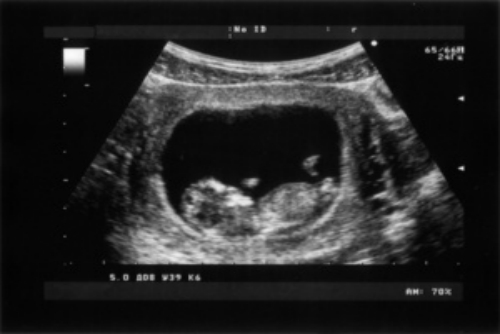

胎兒超聲檢查沒有輻射,胎兒超聲檢查是指在超聲監(jiān)測下,對胎兒的全身各器官進行系統(tǒng)檢查,通常是通過B超檢查方式,針對胎兒的頭部、面部、四肢、心臟等部位,以明確是否存在結構畸形,也可以明確胎兒的發(fā)育狀況。

超聲檢測1

除上述系統(tǒng)畸形外,超聲對胎兒的肺臟、消化系統(tǒng)、泌尿系統(tǒng)等也可以進行檢查,通常情況下,上述系統(tǒng)畸形通過超聲檢查都沒有太大影響。

綜上所述,家長要對胎兒定期進行超聲檢查,以便及早發(fā)現(xiàn)異常情況,如果出現(xiàn)嚴重畸形,要在醫(yī)生幫助下及時終止妊娠。除了定期進行超聲檢查以外,孕婦在孕期應注意休息,避免勞累以及重體力勞動,同時要均衡飲食,為胎兒提供各種營養(yǎng)物質。